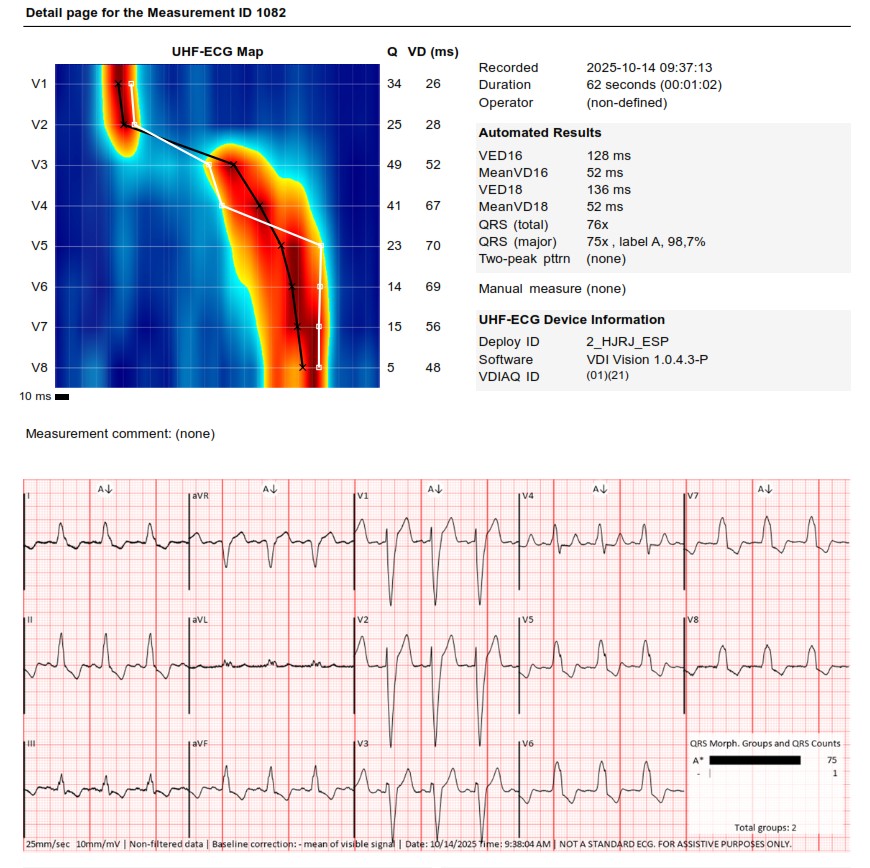

I strongly support HBP, but in this case,the great improvement in QRS didn't correct the asynchrony measured with UHF ECG.We opted for LBBAP despite the RV delay.The final programming AV 70 ms and fusion with native rhythm achieved the best result with UHF ECG(very useful tool)

Challenging LOT CRT case. Final UHF ECG recordings very satisfactory @curilakarol @MirekNavratil1 #Epeeps

An interesting case was shared today. UHF-ECG can help to enhance the decision-making in less textbook-type cases.

These are UHF maps of the two patterns. The second one is a little bit deeper into the septum,